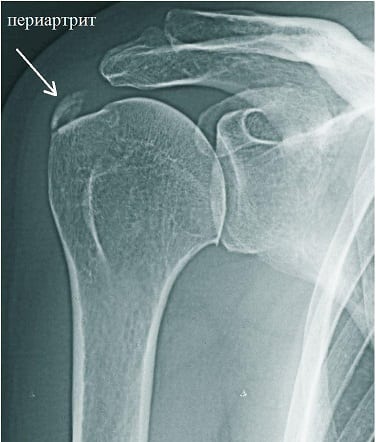

Лечение, симптомы и причины периартрита плечевого сустава

Для диагностирования периартрита проводится инструментальные и биохимические исследования, в том числе и дифференциальные. Лечение чаще консервативное, заключающееся в приеме препаратов, использовании ортопедических приспособлений, соблюдении щадящего режима, выполнении специальных упражнений.